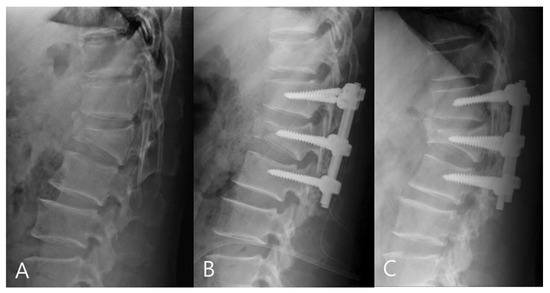

For the mono group, the preoperative mean RKA was 21.56°, and the postoperative mean RKA was 8.13°. The mean correction angle was 13.43° (correction rate 62.31%). The RKA angle decreased from 8.13° to 11.18° (correction loss: 14.18%) in late follow-up. For the poly group, the preoperative mean RKA was 23.18°, and the postoperative mean sagittal plane kyphosis was 11.09°. The mean correction angle was 12.09° (correction rate 52.17%).The RKA decreased from 11.09° to 18.83° (correction loss: 33.42%) in late follow-up. The mono-axial pedicle screw fixation had a better correction rate and reduced the risks of correction loss versus the poly-axial pedicle screw fixation (Figure 3 and Figure 4).

Figure 3.

(A) 58-year-old male patient with L1 burst fracture was treated by mono-axial pedicle screw fixation. (B) Postoperative and (C) final follow-up imaging show good correction and no correction loss.